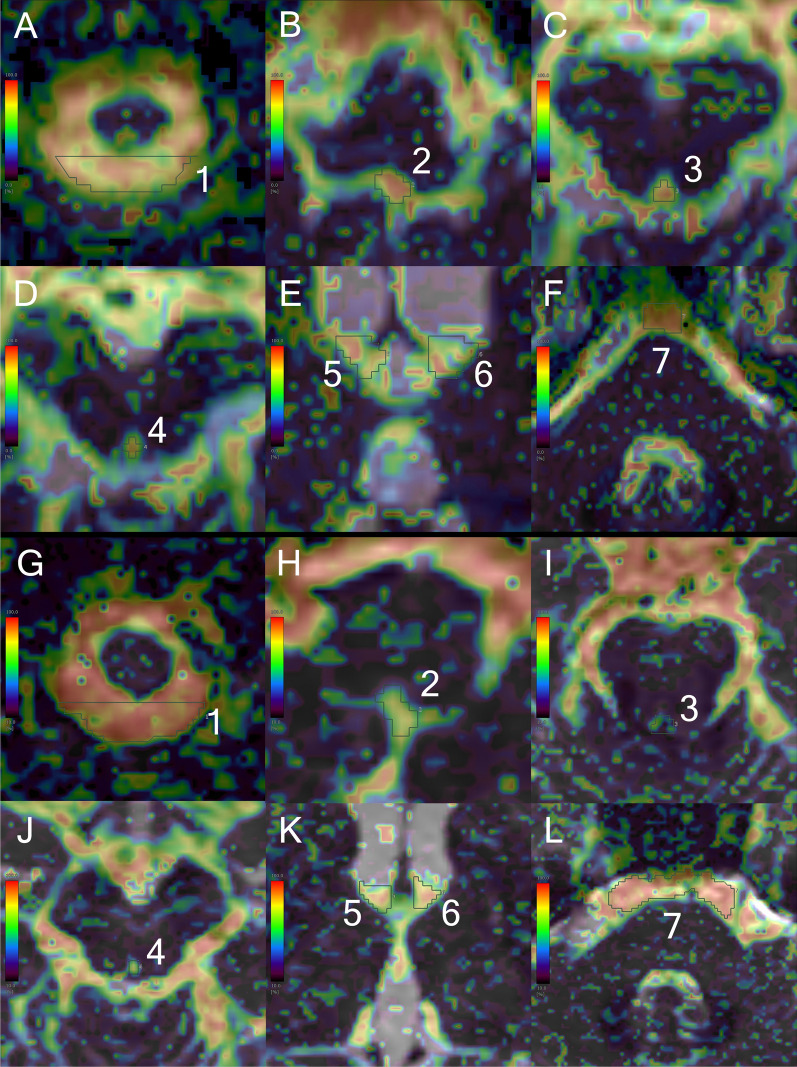

Fig. 3.

Intravoxel incoherent motion f-map in a patient with Hakim’s disease and healthy control. The upper A–F figures show the f-maps focused on seven ROIs in the same patient with Hakim’s disease as Fig. 2, and the lower G–L figures show the f-maps in a representative healthy volunteer with the same age and sex as the patient with Hakim’s disease (73 years old, female). The ROIs were manually drawn at seven points, including the dorsal aspects of the foramen magnum (ROI1) in A and G, foramen of Magendie (ROI2) in B and H, lower part of the cerebral aqueduct (ROI3) in C and I, upper part of the cerebral aqueduct (ROI4) in D and J, left (ROI5) and right (ROI6) foramina of Monro in E and K, and prepontine cistern (ROI7) in F and L. The color bar indicates the magnitude of the f-values on IVIM MRI: red for fast and blue for slow